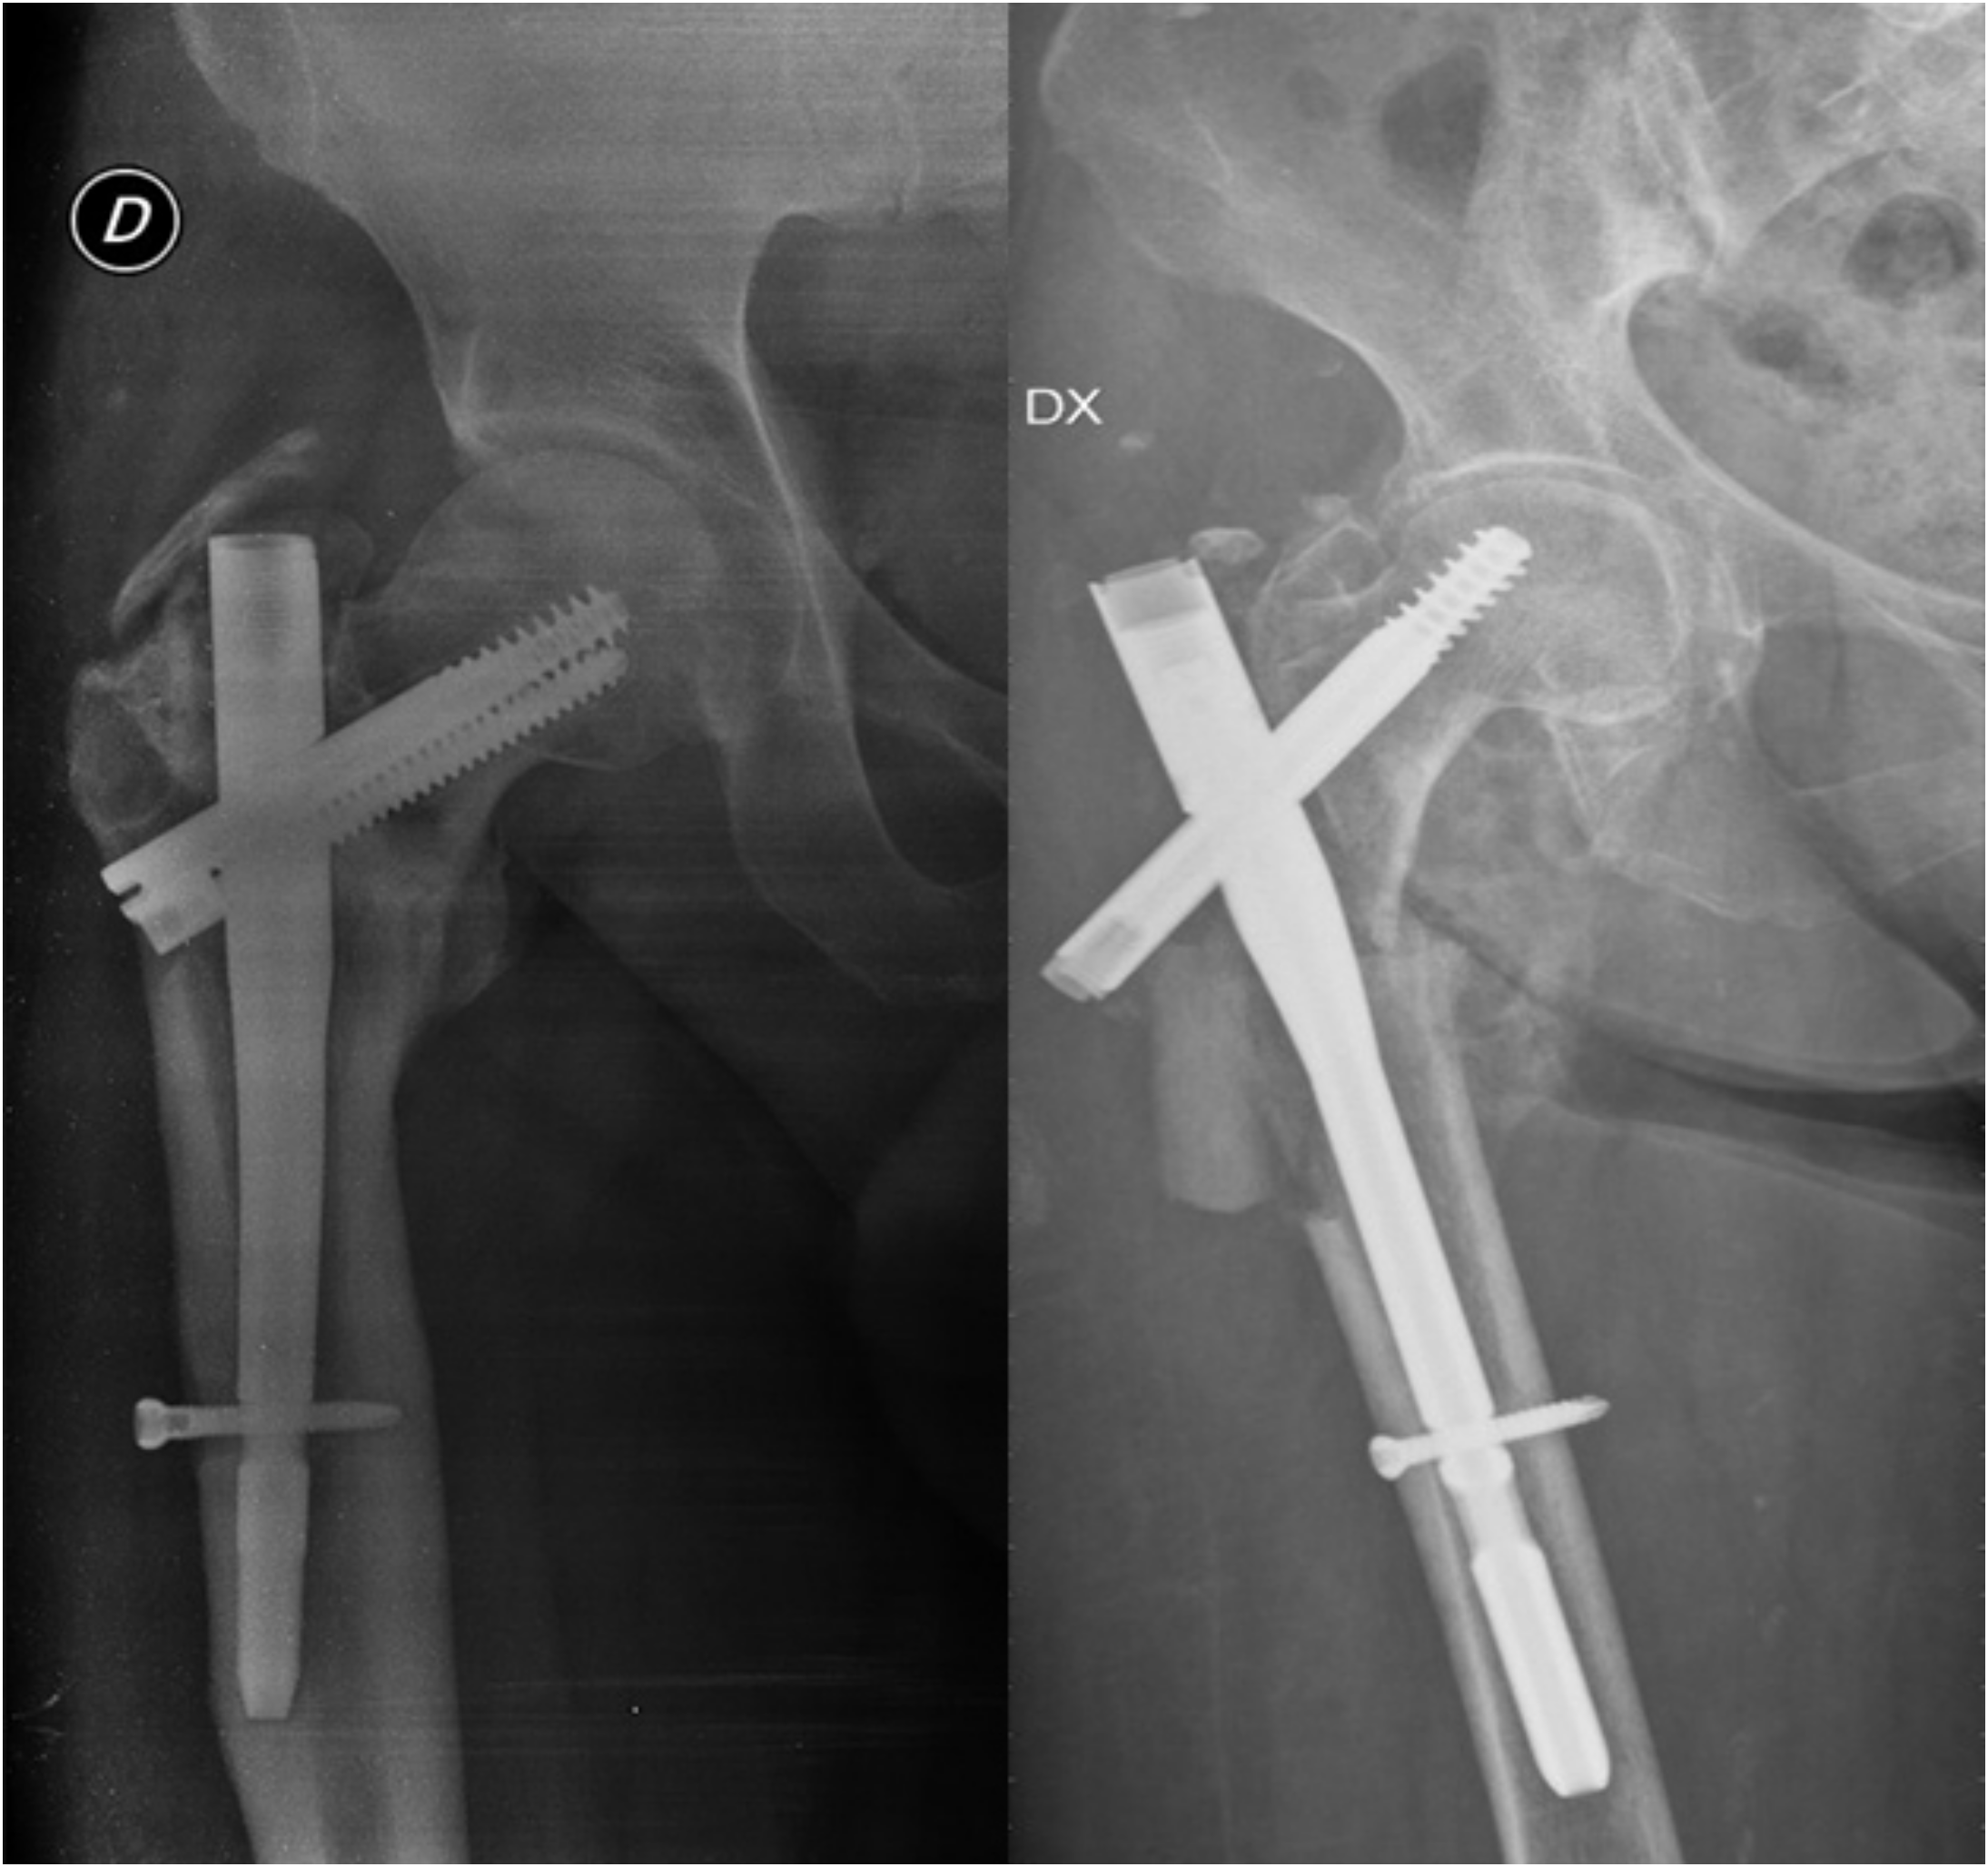

- Cipollaro, L.; Aicale, R.; Maccauro, G.; Maffulli, N. Single- versus double-integrated screws in intramedullary nailing systems for surgical management of extracapsular hip fractures in the elderly: A systematic review. J. Biol. Regul. Homeost. Agents 2019, 33, 175–182. [Google Scholar] [PubMed]

- Jackson, C.; Tanios, M.; Ebraheim, N. Management of Subtrochanteric Proximal Femur Fractures: A Review of Recent Literature. Adv. Orthop. 2018, 2018, 1326701. [Google Scholar] [CrossRef]

- Queally, J.M.; Harris, E.; Handoll, H.H.G.; Parker, M.J. Intramedullary nails for extracapsular hip fractures in adults. Cochrane Database Syst. Rev. 2014, 12, CD004961. [Google Scholar] [CrossRef] [PubMed]

- Parker, M.J.; Handoll, H.H. Gamma and other cephalocondylic intramedullary nails versus extramedullary implants for extracapsular hip fractures in adults. Cochrane Database Syst. Rev. 2010, 8, CD000093. [Google Scholar] [CrossRef]

- Anglen, J.O.; Weinstein, J.N.; American Board of Orthopaedic Surgery Research Committee. Nail or plate fixation of intertrochanteric hip fractures: Changing pattern of practice: A review of the American Board of Orthopaedic Surgery Database. J. Bone Jt. Surg. Am. 2008, 90, 700–707. [Google Scholar] [CrossRef]